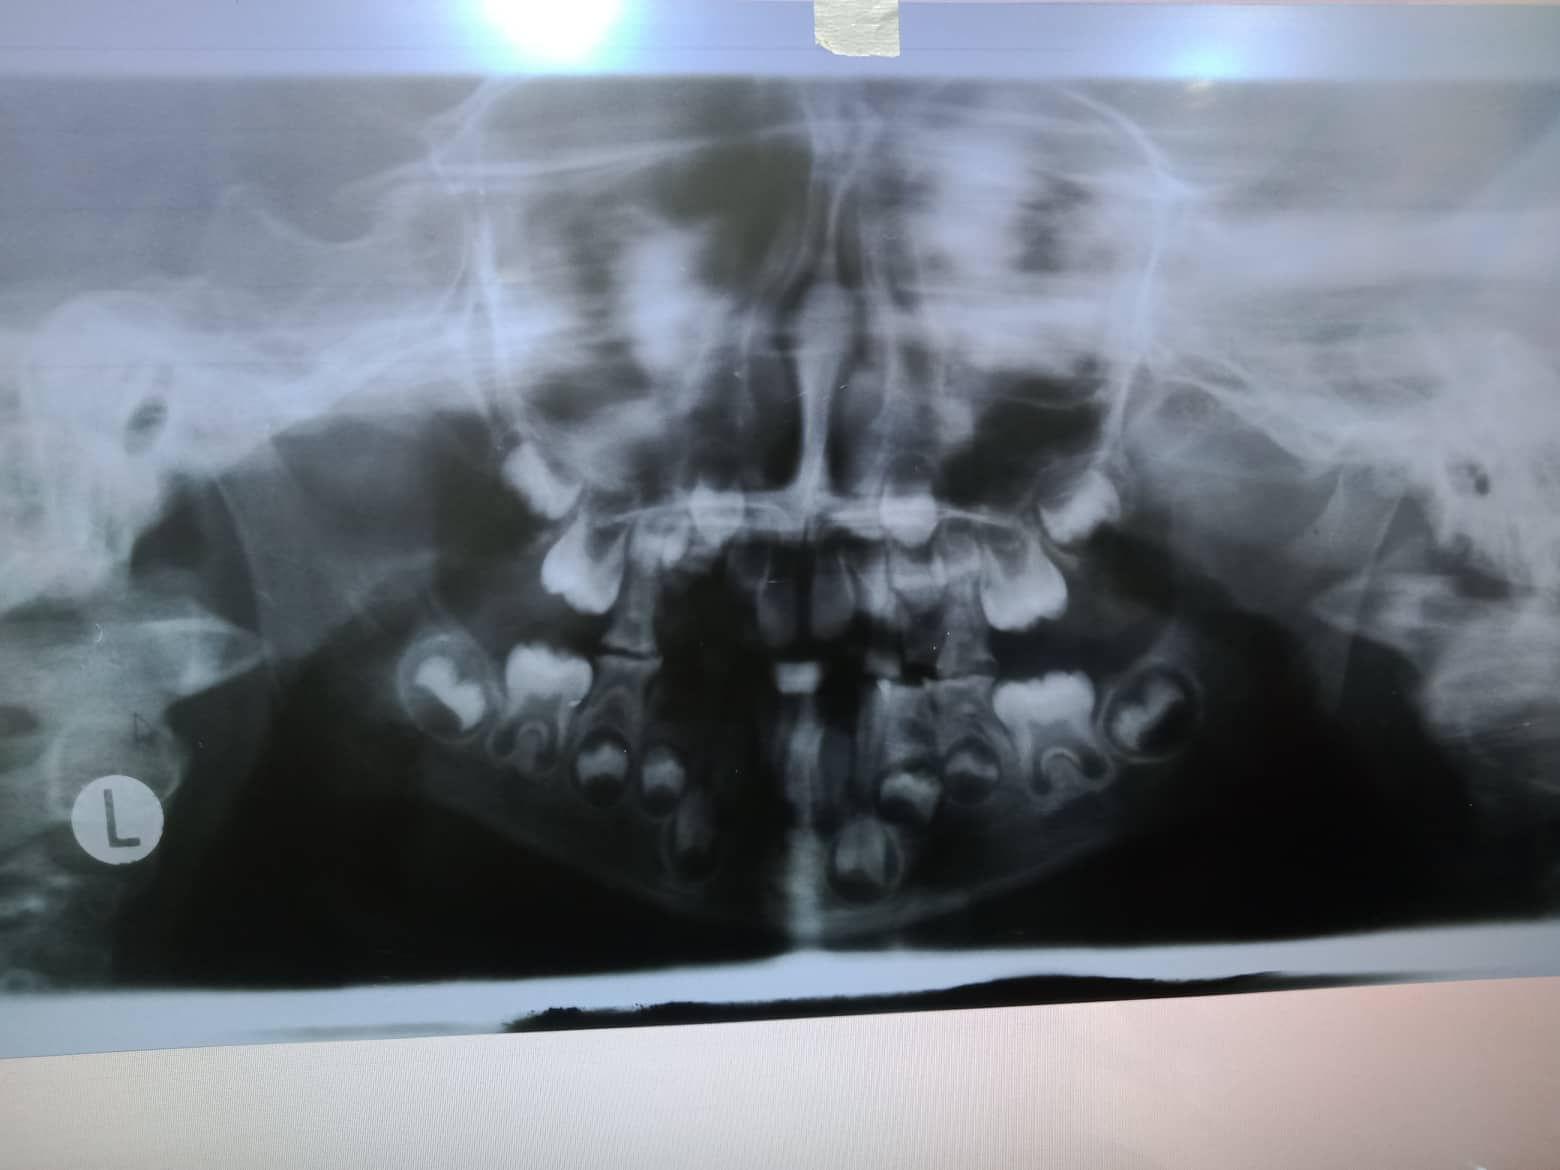

- Precious Dansel

- July 2, 2013

- 11

- Procedure

- 06-11-2018 > UPPER B LEFT, UPPER A LEFT,UPPER A RIGHT - EXO =900 09-08-2018 > LOWER A RIGHT,LOWER A LEFT,LOWER B LEFT- EXO =FREE 09-22-2018 > LOWEER C LEFT AND UPPER B RIGHT - EXO = 600 10-05-2019 > EXO LOWER 2 LEFT = 300 > FILLING #16 = 600 02-04-2020 > CHECK UP 05/21/22- OP+ Fluo 06/14/25 OP (mild) with fluoride LC #46 mesial, #16 occ, #26 occ + caoh, #36 occ +caoh